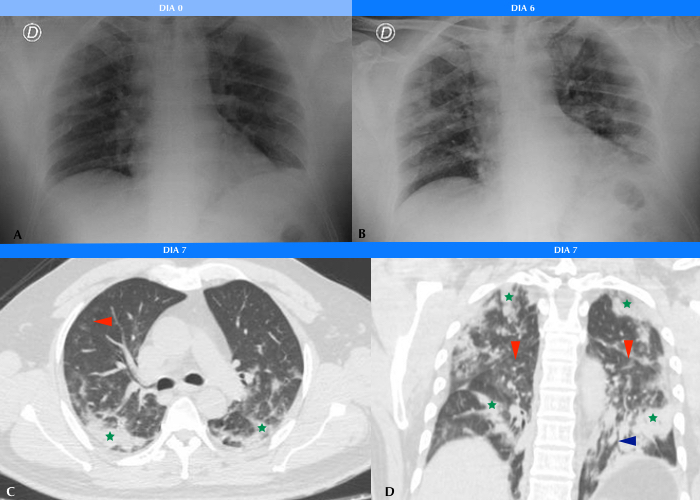

Se realizó TC de tórax a 85 (5,9%) pacientes, de los cuales 11 (13%) fueron positivos por PCR para COVID19. De estos, 9 (81%) manifestaron infiltrados en vidrio esmerilado en el parénquima pulmonar, asociándose además opacidades consolidativas en 4 (36%) de ellos (Figs. 3 y 4). 2 (18%) pacientes no mostraron afectación intersticio-alveolar en su evolución. La TC se realizó a pacientes cuya clínica no era acorde a los hallazgos de Rx y a aquellos con evolución tórpida (81%). En total, a 8 (72%) pacientes COVID-19 positivos se les realizaron ambos métodos imagenológicos.

En cuanto a la distribución, en los cortes axiales se encontró que siete pacientes presentaron opacidades o consolidaciones periféricas, o ambas (Figs. 5 y 6).

La cantidad de lóbulos afectados fue variable. Un paciente presentó afectación lobar única, uno afectación bilobar, cuatro afectación de tres lóbulos y dos pacientes de cuatro lóbulos. Únicamente un paciente sufrió compromiso panlobar (Fig. 7). Los lóbulos pulmonares con mayor afectación fueron los superiores: siete pacientes tuvieron afectación del lóbulo superior derecho y ocho pacientes del lóbulo superior izquierdo. Cabe mencionar, además, que ocho pacientes tuvieron afectación bilateral y uno unilateral.

En un paciente se encontró patrón en empedrado (Fig. 8) y en dos pacientes opacidades redondeadas en vidrio esmerilado (Tabla 1).

Como hallazgos atípicos, se evidenciaron derrame pleural en dos pacientes y neumotórax en uno, cuya causa fue atribuida a complicación tras la colocación de un marcapasos (Fig. 9). No se evidenciaron adenomegalias mediastinales.